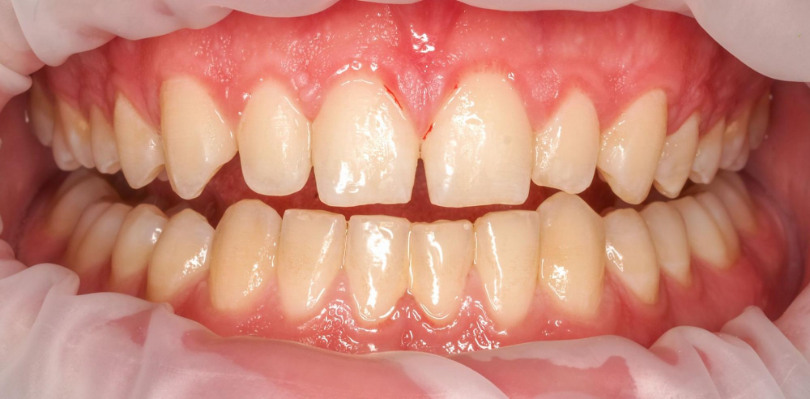

Pacjent zgłaszał się na regularne, co półroczne higienizacje. Wybarwienie płytki nazębnej na pierwszej wizycie ujawniło silne zaleganie płytki nazębnej dojrzałej, kwasowej, gęsto otaczającej zęby (kolor fioletowy). Z każdą kolejną wizytą widać było poprawę higieny i sukces działań higienistki stomatologicznej oraz motywacji własnej Pacjenta. Na trzeciej wizycie po wybarwieniu dostrzegalny jest już tylko delikatny, świeży biofilm. Dzięki technologii GBT posiadamy narzędzia do monitorowania higieny Pacjenta i pozytywnego wzmacniania jego dobrych nawyków.